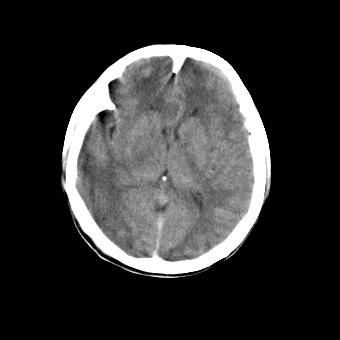

标题: CT16478:男 头晕 恶心 呕吐 [打印本页]

标题: CT16478:男 头晕 恶心 呕吐

蛛网膜下腔出血可能性大!

病人不合作,图像质量差,右额叶及后纵裂可见高密度影,建议复查。

1.额叶显示密度不均匀,且右侧内见小片稍高密度影, 图像效果差些,不好定?

2.纵裂密度增高,部分脑回密度似乎也增高,蛛网膜下腔出血。

蛛网膜下腔出血可能?不知道他的肢体症伏如何!

病人不合作,图像模糊,大脑镰及纵裂池后部密度增高;考虑:蛛血?